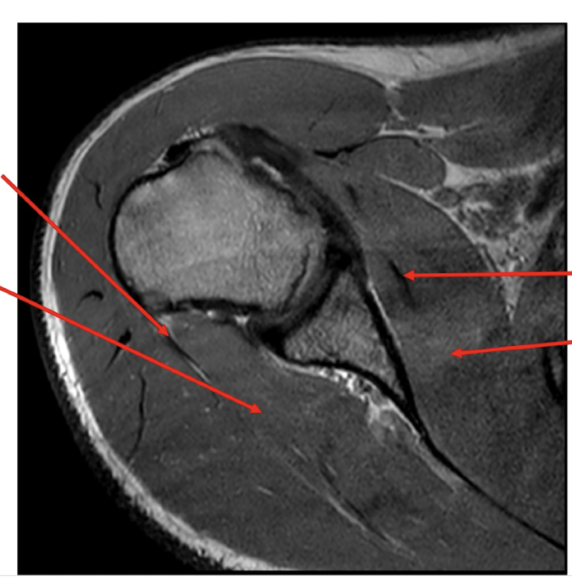

Sequence + pathology?

• PD, PDFS

• Path = supraspinatus tendon tear

• -  You can follow the tendon and see that it stops just above the humeral head rather than

attaching to the lateral aspect of the head.

• -  More prominent of the PDFS you can see high signal around the lateral aspect of the humerus

indicative of a pathological process occurring because of the tear.